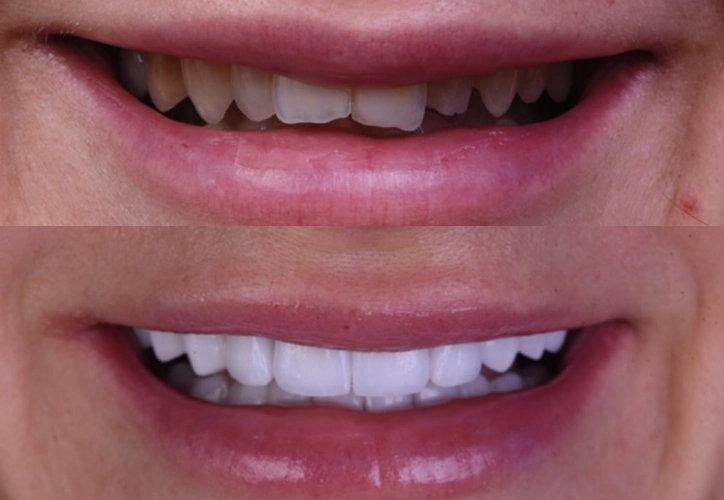

Fațete dentare

coroane protetice